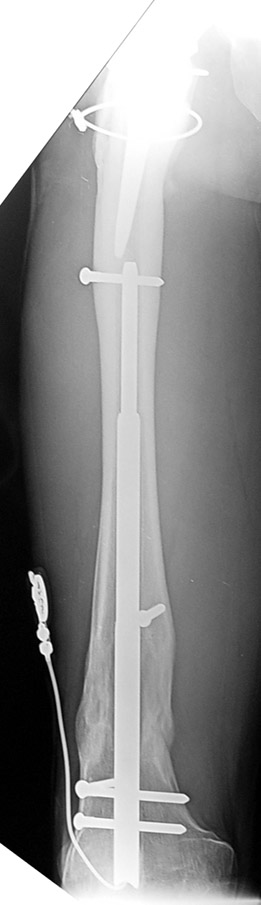

Case 1